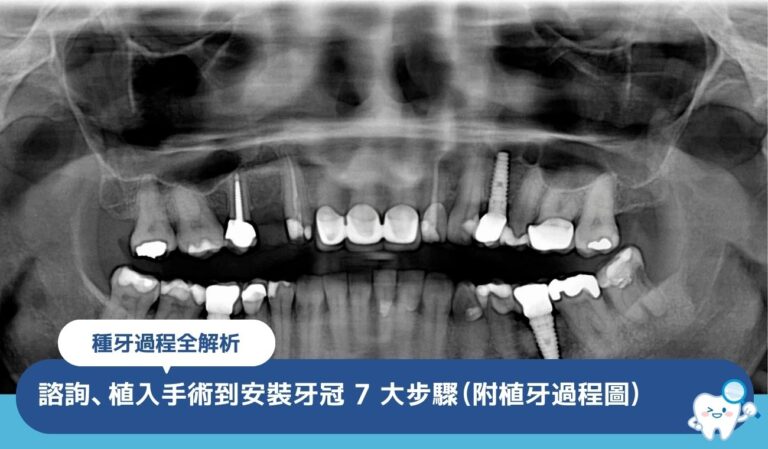

想知道種牙過程需要多久?本文詳細拆解從 牙齒 評估、植牙手術到安裝牙冠的 7 大步驟,並附上詳細植牙過程時間表,助您安心展開缺牙修復療程。